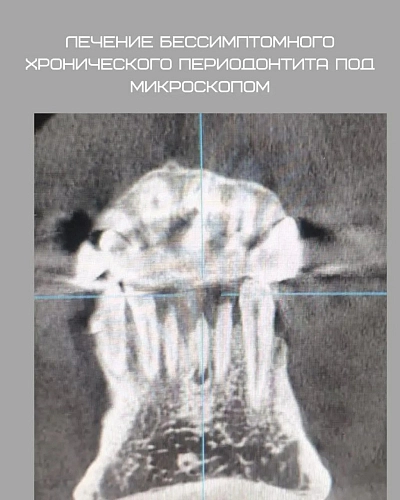

Рассмотрим клинический случай: пациент обратился с бессимптомным течением хронического периодонтита. Мы решили провести ревизию корневых каналов под микроскопом для устранения патогенной микрофлоры. Спустя три месяца после лечения мы наблюдаем положительные результаты — источник костного разрежения значительно уменьшился, а инфекция была успешно устранена.

Лечение бессимптомного хронического периодонтита под микроскопом демонстрирует свою эффективность: положительная динамика наблюдается уже через 3 месяца.